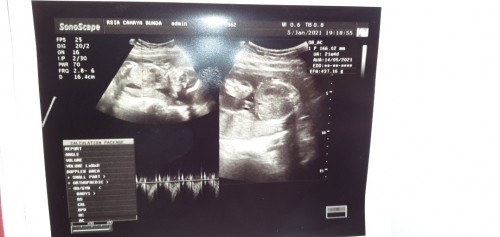

Usg 20w3d ❤

Assalamu'alaikum nak, Alhamdulillah kamu sehat yaa sayang. MasyaAllah BBmu naik bgt, jadi itungannya maju seminggu hihi. Loveyou nak bayik 🥰